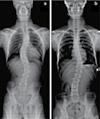

후유증 허리통증 / 허리 디스크 / 관절염 / 좌골신경통 / 고관절, 발목, 손목 통증 ▪ ▪ ▪ ▪ ▪ ▪ ▪ ▪ ▪ 최첨단 목/허리 디스트 치료기기 최신형 디지털 X-ray 시설 Therapeutic Massage ▪초음파, 전기치료 Gonstead Chiropractic 교정치료 치료 진료과목 교통사고 치료 전문 자동차 보험 건강 보험 상해 보험 Southern California University of Health Science Doctor of Chiropractic 콜로라도주 척추신경 보드 정회원 캘리포니아주 척추신경과 보드 정회원 National Board 척추신경과 정회원 손석기 D.C. 원장, 척추신경 전문의 chiro1health@gmail.com Open Hours 월/수/금 9am-6pm 화/목: 2pm-6pm 청소년을 위한 척추교정 프로그램

손, 발, 다리의 통증, 저림, 근육약화감, 감각상실 (편)두통 / 불면증 / 어지러움 / 턱관절 장애(TMJ) 척추측만증(Scoliosis) / 척추협착증 / 허리수술

후유증 / 목 통증 / 목 디스크 / 오십견 / 어깨통증